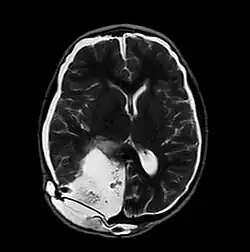

MRI of Pseudomeningocele in 8 years old male patient

A pseudomeningocele is an abnormal collection of cerebrospinal fluid (CSF) that communicates with the CSF space around the brain or spinal cord. In contrast to a meningocele, in which the fluid is surrounded and confined by dura mater, in a pseudomeningocele, the fluid has no surrounding membrane, but is contained in a cavity within the soft tissues.